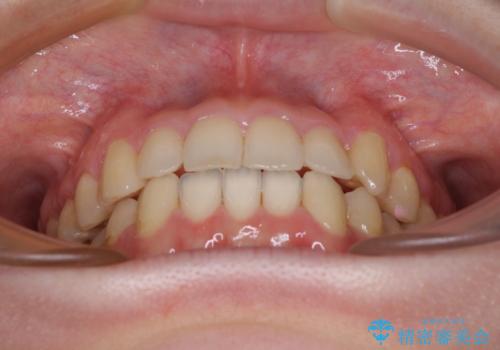

思っていた以上に上顎歯列を後方に移動させることができ、すっきりとした口元に仕上げることができました。

口元を見ると抜歯をして突出感を改善するような状態ではなかったため、上顎歯列のデコボコを整えて、歯列全体を後方に移動させることでバランスを取ることとしました。